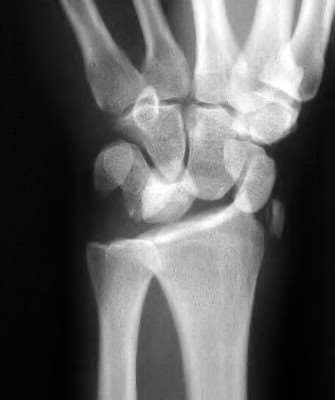

A 22-year-old male falls onto an outstretched hand and sustains a displaced fracture through the proximal pole of the scaphoid. Avascular necrosis of the proximal pole is highly likely due to the disruption of its primary vascular supply. Which vessel provides this critical retrograde perfusion?

Explanation

The primary blood supply to the scaphoid is from the dorsal carpal branch of the radial artery, which enters the dorsal ridge of the scaphoid at the waist and courses proximally. This retrograde blood flow makes proximal pole fractures highly susceptible to avascular necrosis and nonunion. The superficial palmar branch provides a minor supply (about 20%) to the distal pole.